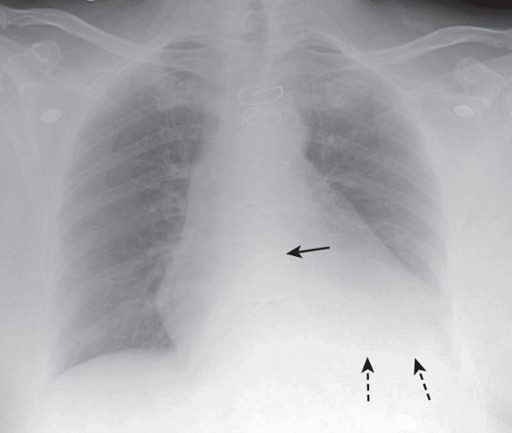

Pleural Effusion

Fluid accumulation in the pleural cavity visible on chest imaging, typically seen at the costophrenic angle.

Penetration

The degree of penetration is adequate since we can see the spine (solid white arrows) through the heart.

Poor Inspiration

Only eight posterior ribs are visible on this frontal chest radiograph.

A poor inspiration may “crowd” and therefore accentuate the lung markings at the bases (black arrows) and may make the heart seem larger than it actually is.